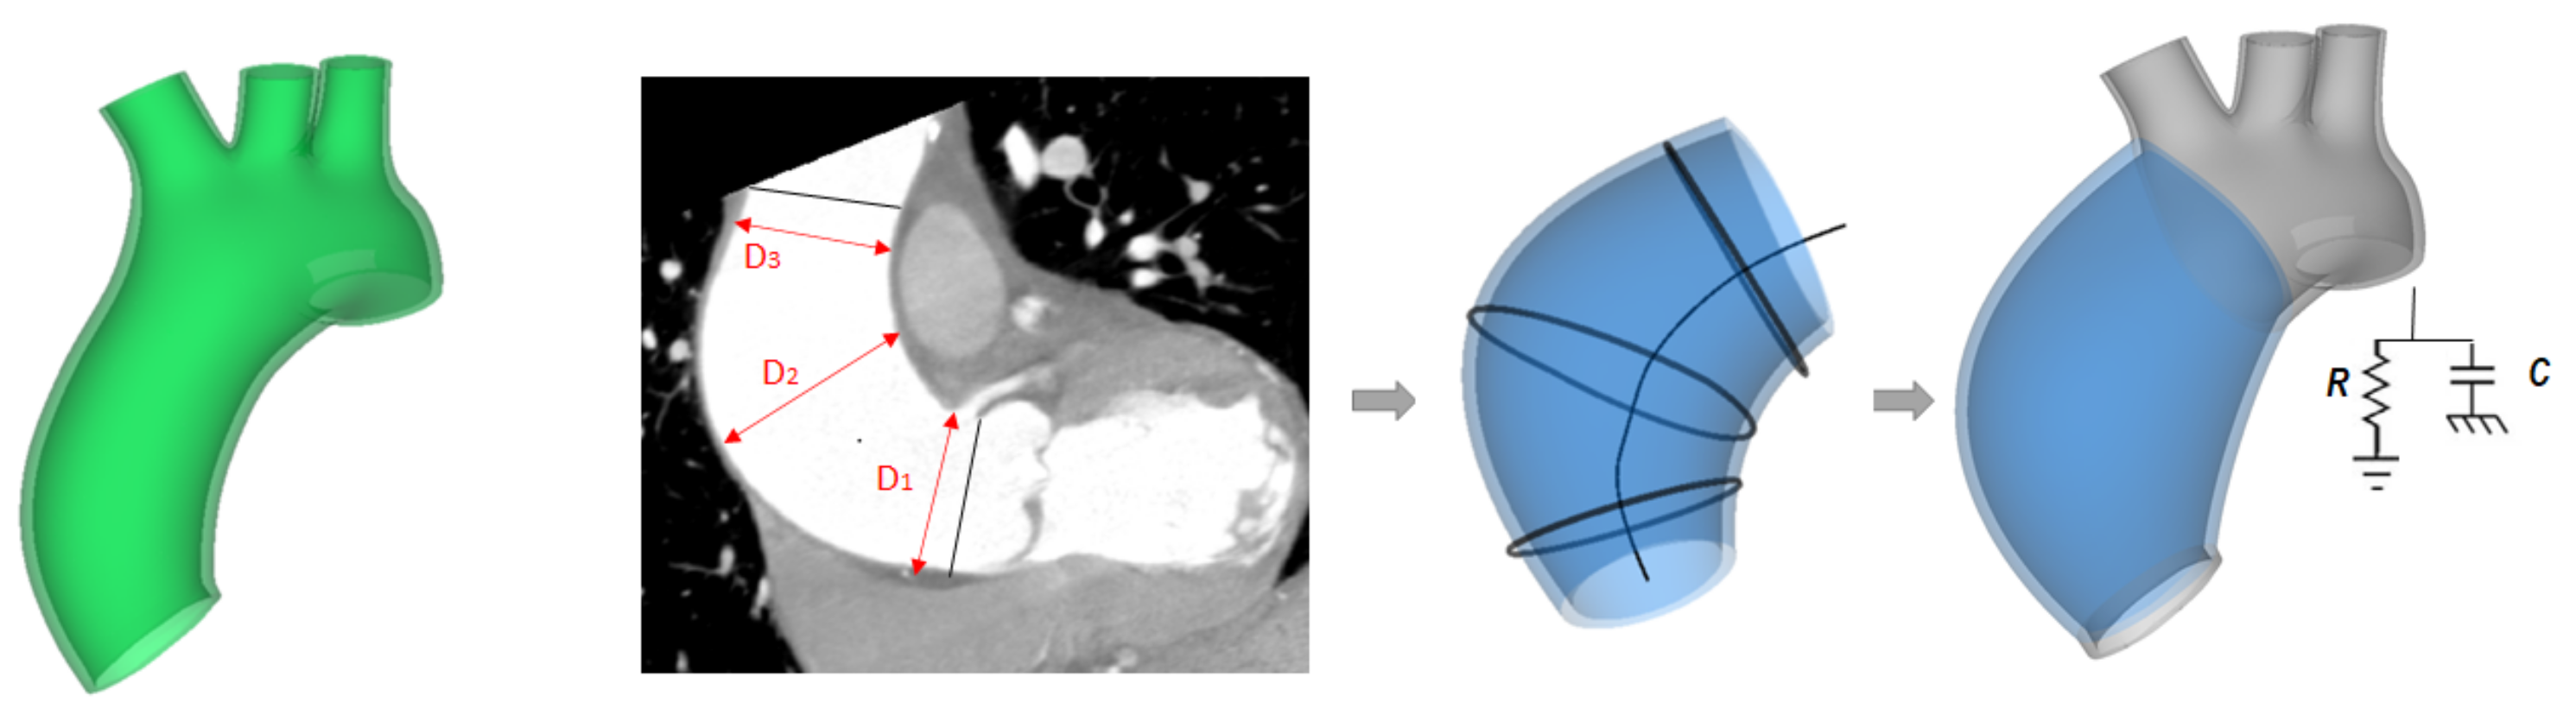

2.2. ATAA Reconstruction

2.4. LHHM Model and Adaption to ATAA